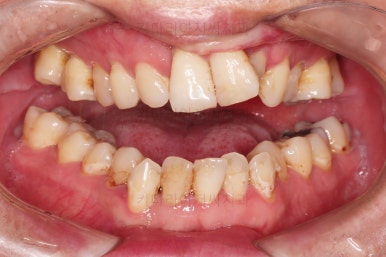

1. 초진 시 입안의 모습

부산구순구개열교정 키다리아저씨치과에 처음 내원하셨을 당시의 입안의 모습입니다.

구순구개열 환자분의 일반적인 입 안의 특징은 다음과 같습니다.

골 결손부위의 치아 결손이 빈번하다.

구개열 봉합술을 어린 나아이에 받기 때문에, 해당 부위의 상흔이 남는다.

상흔의 영향으로(피부 상처도 일반 피부 보다는 상처가 아문 부위가 더 단단하죠.) 입천장의 잇몸이 굉장히 단단하다.

그래서 가로폭의 성장이 잘 되지 못하여 악궁(치아가 배열된 U자 형태)이 협착된 경우가 많다.

공간 부족으로 치열이 매우 삐뚠 경우가 많다.

공간 부족과 악궁 형태 등으로 인해 부정교합이 함께 나타난다.

골 결손부위 근처의 치아는 뼈가 약한 경우가 많아 튼튼하지 못하고 만지면 흔들리는 경우가 많다.

이번 환자분도 이와 같은 일반적인 특징이 그대로 나타나 있었습니다.

양측성 구순구개열이었으므로 작은 앞니(대문니와 송곳니 사이)가 양쪽 다 결손이었고, 또 다른 이유로 아래 앞니도 1개 없는 상태였습니다.